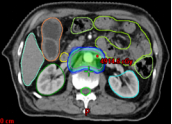

病例展示二:前列腺癌

XXX,男,64岁,主诉:间断性会阴部疼痛10月,确诊为前列腺癌7月。盆腔核磁:前列腺偏左侧异常强化占位,多考虑前列腺Ca,并左侧精囊腺受侵可能,盆腔左侧略大淋巴结。前列腺癌标志物提示:TPSA 88.67 ng/ml,FPSA 3.84 ng/ml。病检:(前列腺穿刺组织左侧)前列腺腺泡腺癌,Gleason评分4+3=7分;(前列腺穿刺组织右侧)Gleason评分3+3=6分。诊断:1、前列腺恶性肿瘤 双侧 腺泡腺癌Gleason评分4+3 =7分 cT3bN0M0 III期 KPS评分:80分。治疗方案:醋酸戈舍瑞林缓释植入剂 10.8mg 皮下注射、比卡鲁胺胶囊 50mg 口服 1次/天”全身治疗,并行前列腺癌碳离子治疗,剂量:57.6 Gy(RBE)/16 Fx。